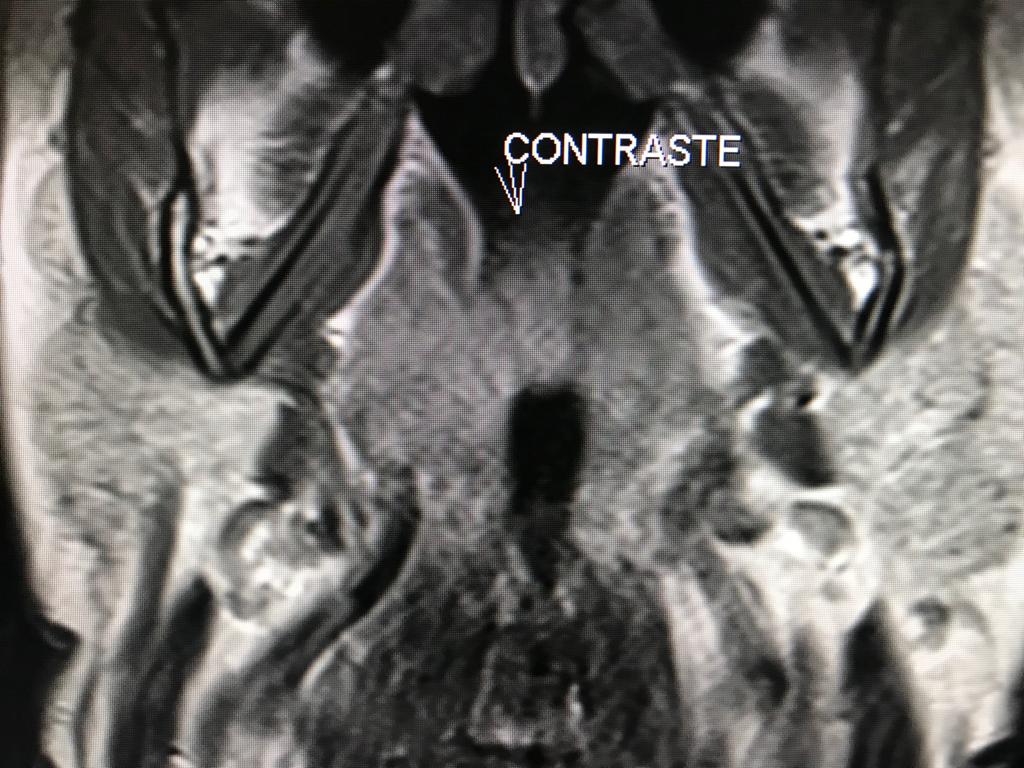

RM CEREBRAL

RM CEREBRAL Meningioma Lipomatoso: Es una variante atípica del meningioma. Los meningiomas constituye el tumor  intracraneal primario más frecuente (15-20%) y el tumor extraparenquimatoso más frecuente en el compartimento supratentorial en el adulto. Es por tanto una...